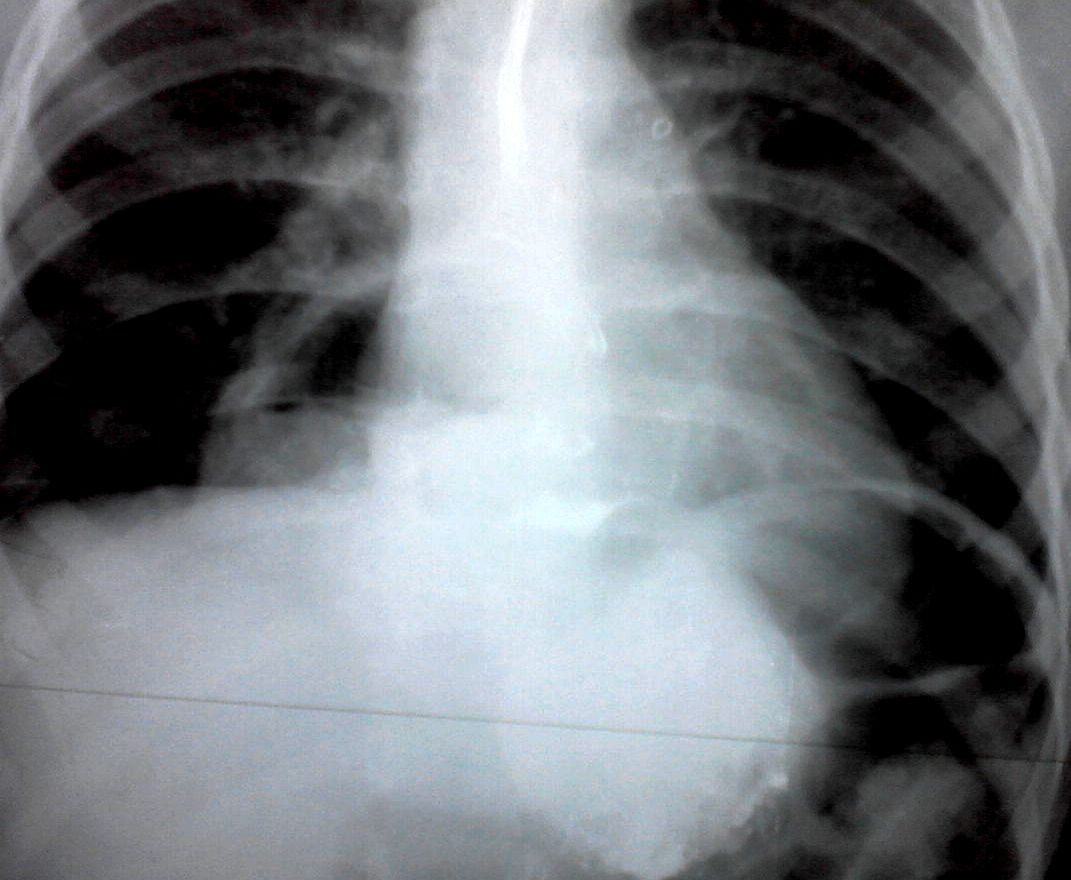

Девочка 4-х лет, жалобы на длительный кашель (оеоло 1-го месяца). В поликлинике выполнена рентгенография органов грудной клетки, выявлены изменения (какие - пока не скажу). Госпитализирована. Направлена на УЗИ сердца. При УЗИ - в самом сердце - патологии не выявлено, но позади него к правому предсердию прилежит полостное образование с акустически неоднородным содержимым.

Образование в средостении - диафрагмальная грыжа